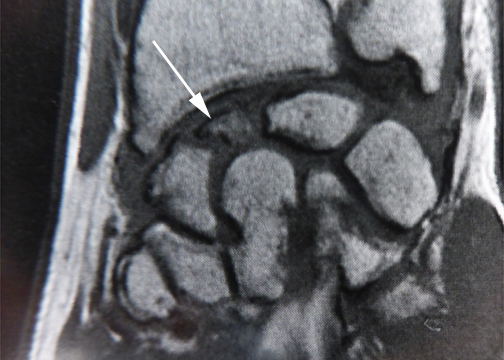

Pseudarthrose d’un petit fragment de pôle proximal du scaphoïde.

Ce petit fragment est mal vascularisé et consolide très difficilement.